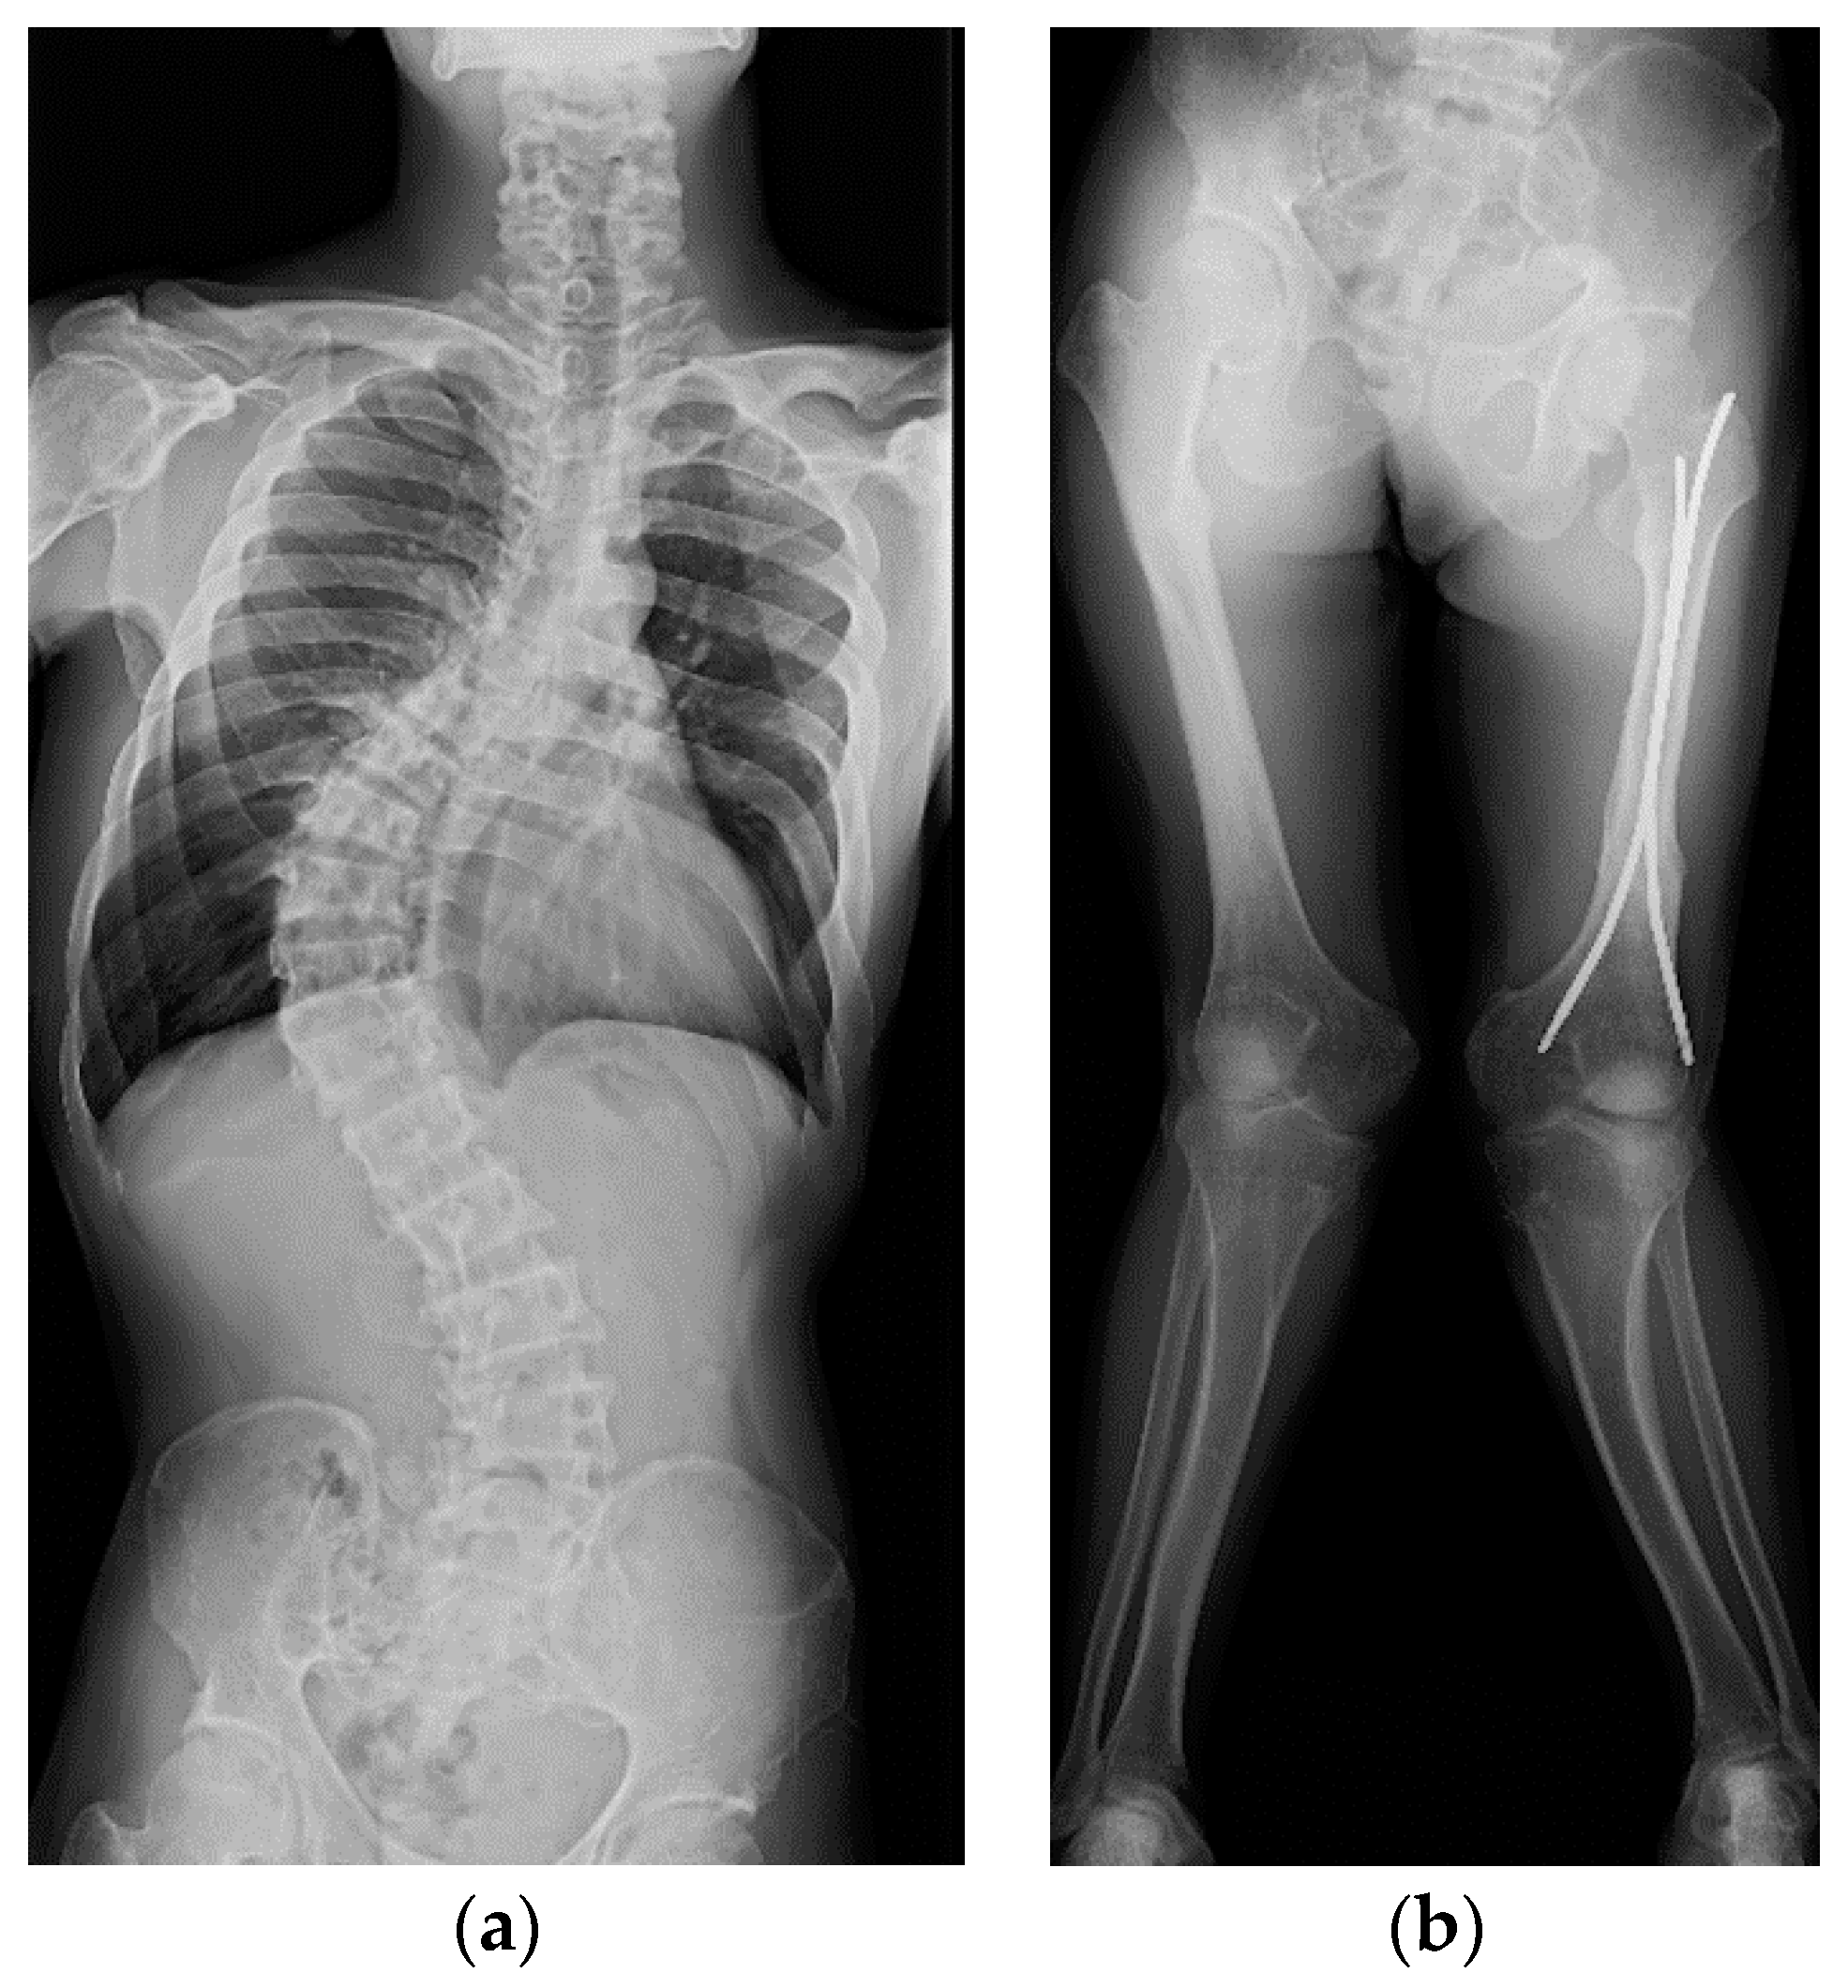

2. Case Presentation

2.1. Patient 1

2.2. Patient 2

2.3. Patient 3